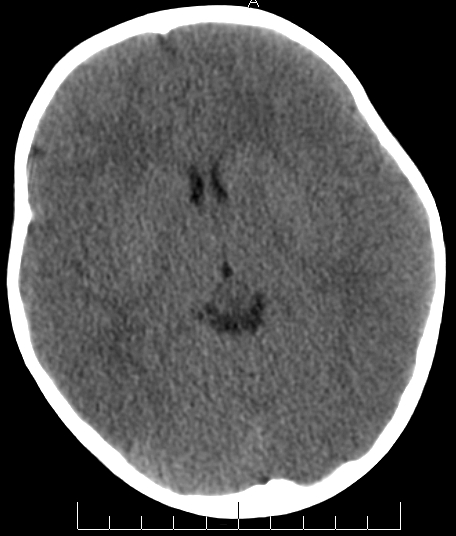

女,3岁,头部外伤一小时。半卵圆中心低密度是什么意思,病灶?侧脑室?请指教。

正常表现

脑白质

幼儿正常脑白质表现,长期观察,必要时mr

从层面看不是侧脑室,考虑低密度变,建议mri。

不是侧脑室,考虑正常脑白质。为慎重,建议mr!